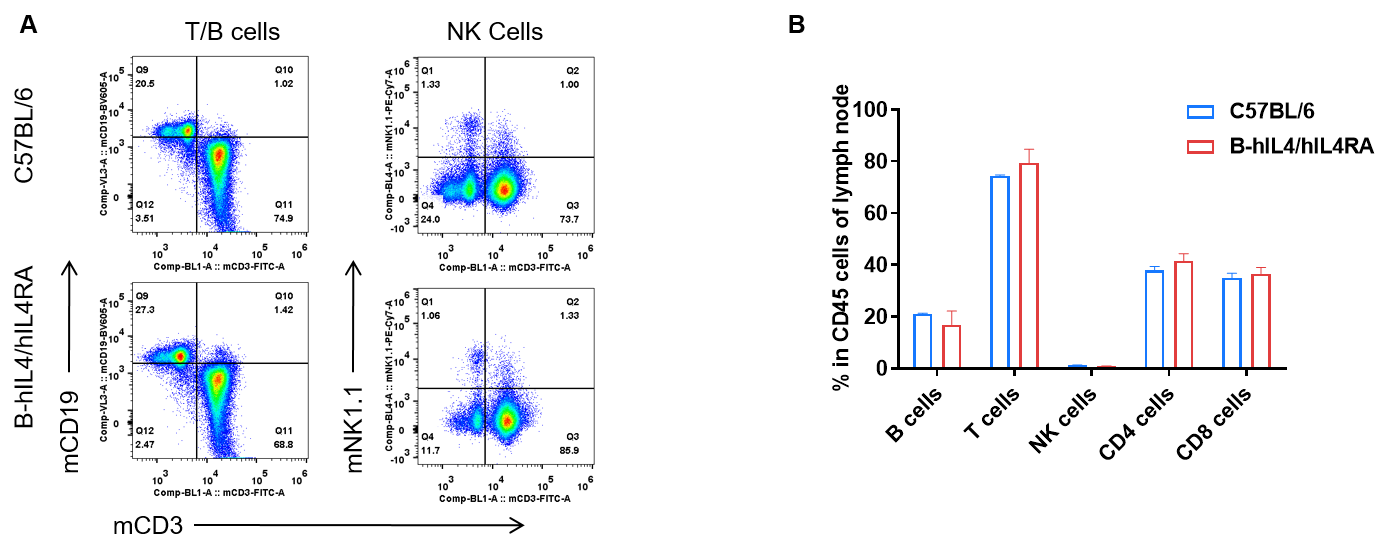

Analysis of subpopulation of leukocytes in lymph node by FACS. Lymph nodes were isolated from female C57BL/6 and B-hIL4/hIL4RA mice (n=3, 10-week-old). Flow cytometry analysis of the lymph nodes was performed to assess leukocyte subpopulations. A. Representative FACS plots. Single live CD45+ T cells were used for further analysis as indicated here. B. Results of FACS analysis. Percent of T, B, and NK cells in homozygous B-hIL4/hIL4RA mice were similar to those in the C57BL/6 mice, demonstrating that introduction of hIL4 and hIL4RA in place of its mouse counterpart does not change the overall development, differentiation or distribution of these cell types in lymph node. Values are expressed as mean ± SEM.